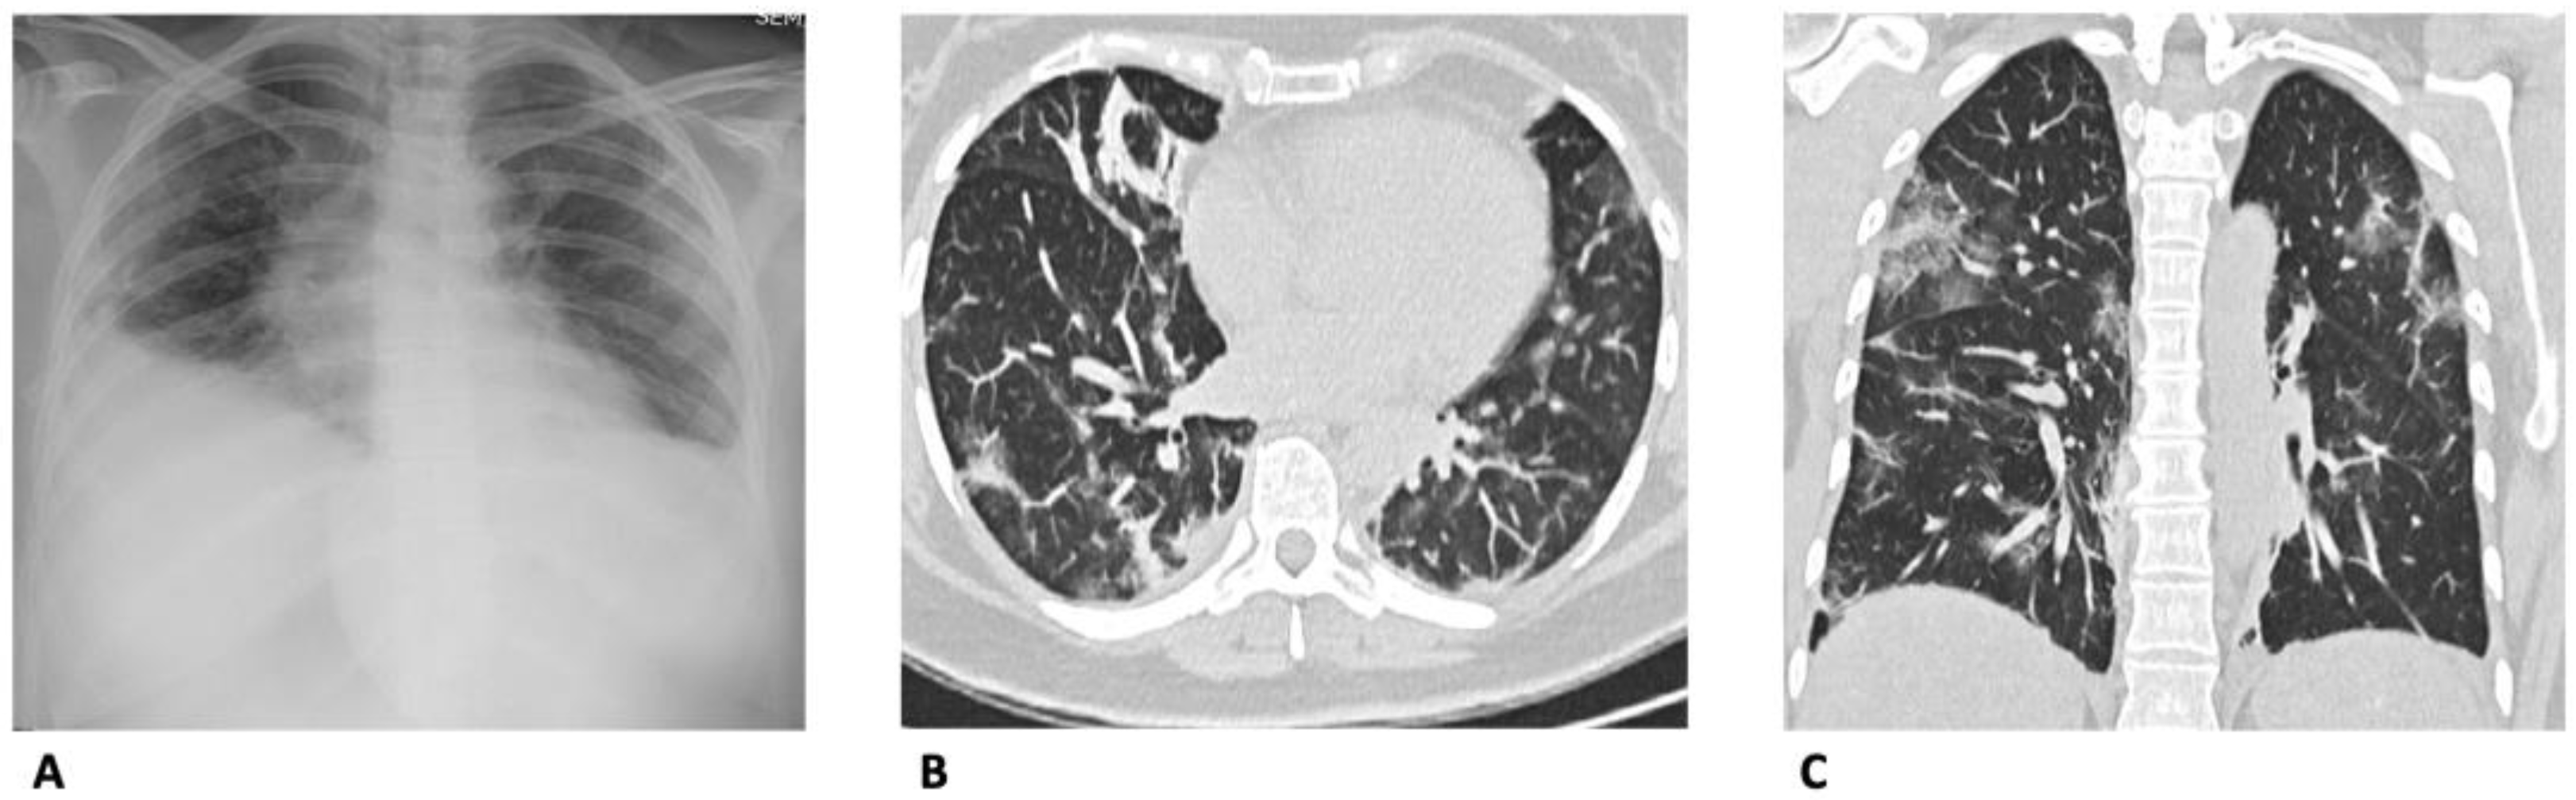

3. Chest X-ray (CXR)

4. Computed Tomography (CT)